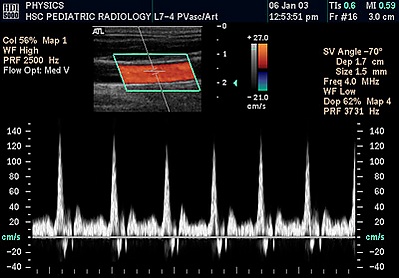

В современных ультразвуковых сканерах доплерография, как правило, производится в дуплексном или даже триплексном режиме, то есть сначала в В-режиме находится сосуд, потом на нём устанавливается область (контрольный объём) измерения данных соответствующая нужной глубине сканирования и получается спектр потока.

Предназначена для оценки движения подвижных сред. В частности, кровотока в относительно крупных сосудах и камерах сердца, стенок сердца. Основным видом диагностической информации является спектрографическая запись, представляющая собой развертку скорости кровотока во времени. На таком графике по вертикальной оси откладывается скорость, а по горизонтальной — время. Сигналы, отображающиеся выше горизонтальной оси, идут от потока крови, направленного к датчику, ниже этой оси — от датчика. Помимо скорости и направления кровотока, по виду доплеровской спектрограммы можно определить характер потока крови: ламинарный поток отображается в виде узкой кривой с четкими контурами, турбулентный — широкой неоднородной кривой.

Основано на кодировании в цвете значения доплеровского сдвига излучаемой частоты. Методика обеспечивает прямую визуализацию потоков крови в сердце и в относительно крупных сосудах. Красный цвет соответствует потоку, идущему в сторону датчика, синий — от датчика. Темные оттенки этих цветов соответствуют низким скоростям, светлые оттенки — высоким. Недостаток: невозможность получения изображения мелких кровеносных сосудов с маленькой скоростью кровотока. Достоинства: позволяет оценивать как морфологическое состояние сосудов, так и состояние кровотока по ним.

- Импульсный доплер (PW, HFPW) — импульсный доплер (Pulsed Wave или PW) применяется для количественной оценки кровотока в сосудах. На временной развертке по вертикали отображается скорость потока в исследуемой точке. Потоки, которые двигаются к датчику, отображаются выше базовой линии, обратный кровоток (от датчика) — ниже. Максимальная скорость потока зависит от глубины сканирования, частоты импульсов и имеет ограничение (около 2,5 м/с при диагностике сердца). Высокочастотный импульсный доплер (HFPW — high frequency pulsed wave) позволяет регистрировать скорости потока большей скорости, однако тоже имеет ограничение, связанное с искажением доплеровского спектра.